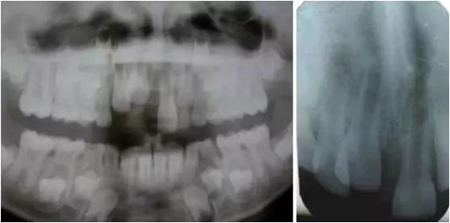

影像學檢查:根尖片以及全景片(圖2)提示牙槽骨骨折,根尖挫入至唇側骨板或鼻底。根尖片提示牙11,12 和21根尖發(fā)育不完全,呈喇叭口狀。受累牙的根管壁薄且不完全成形(圖2)。牙片顯示沒有冠折和根折。

( 圖2)